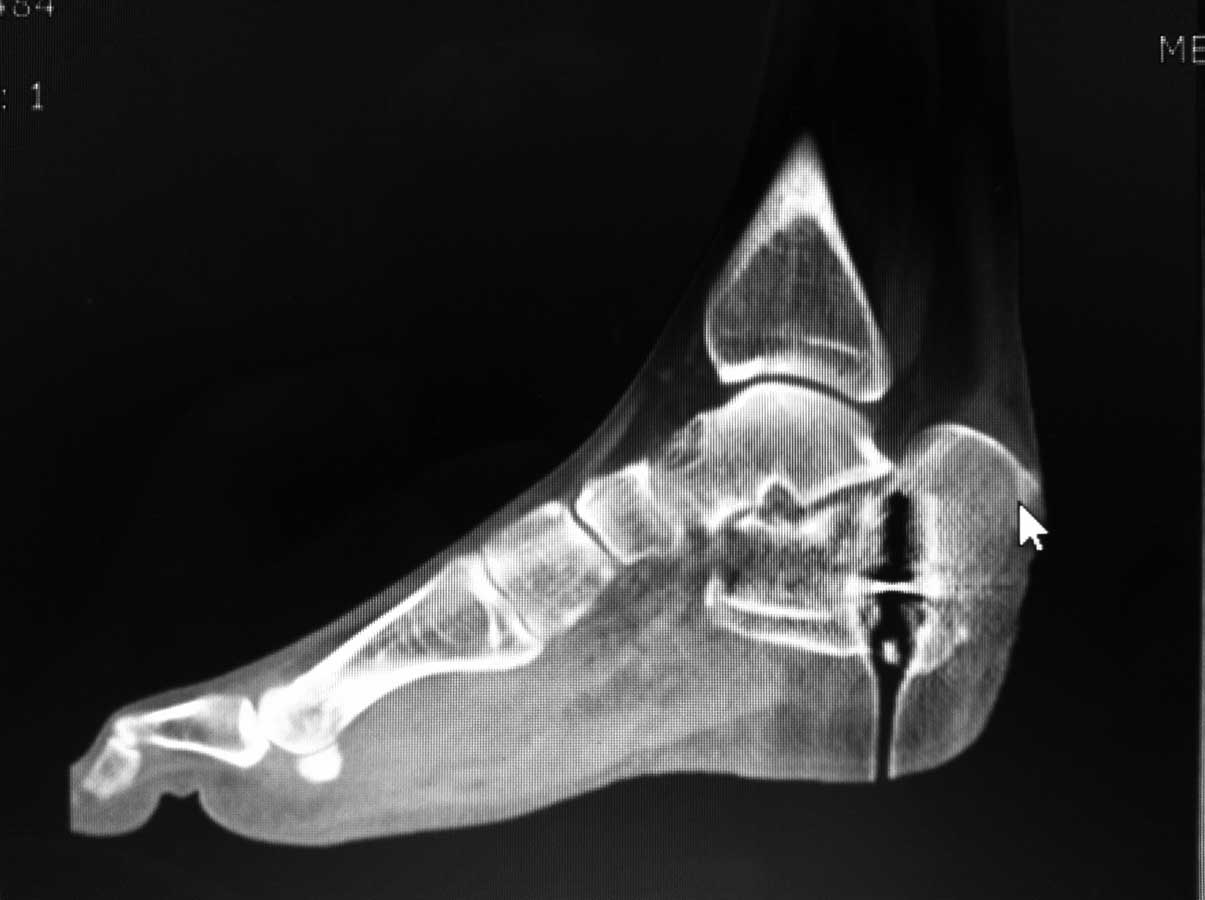

КТ

[ Ответить ]